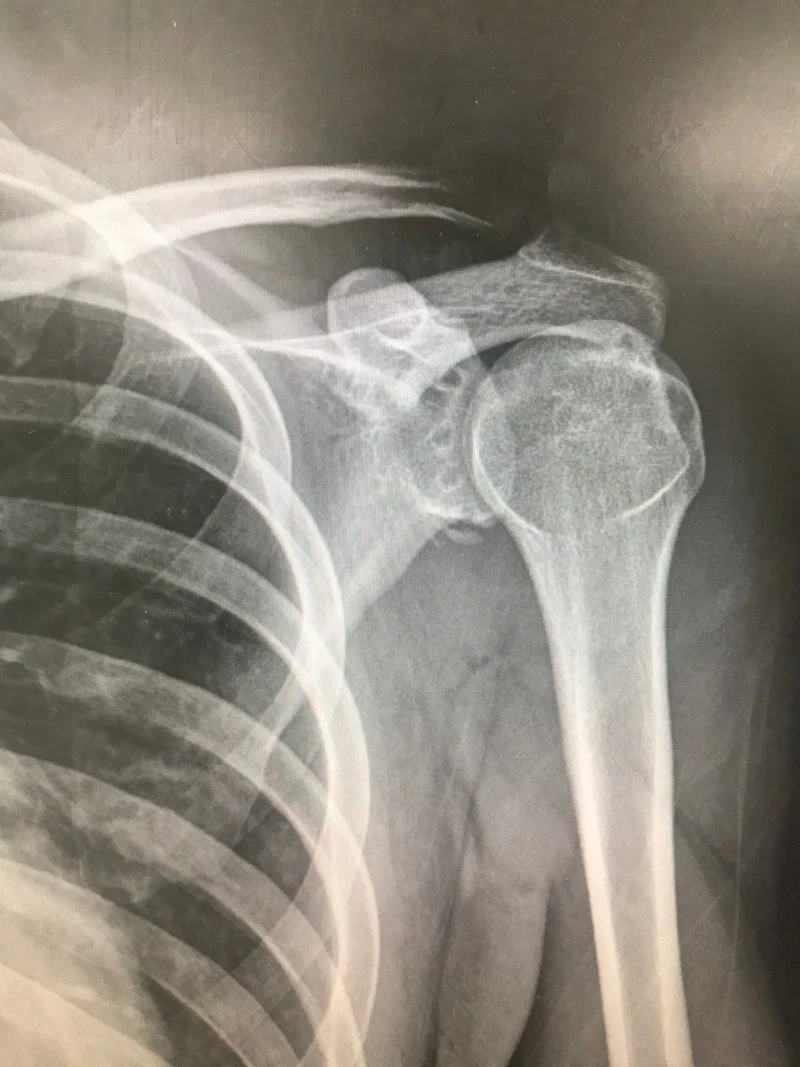

유쾌하고 출근해서 상쾌하게 진료하는데, 스무 살 청년이 축 처진 어깨를 붙잡고 응급실에 들어왔어요. 통증의 극심함이 관상에 온전히 드러납니다. 습관성 어깨 탈구로 수술도 받았고, 2주 전에도 재발하여 견인 치료를 받았다네요. 내원 40분 전에 운동하며 왼팔에 힘을 주다가 다시 어깨가 궤도를 이탈했답니다.

아파서 눕지도 못하길래 진통제부터 투여했고요. 통증은 진정되었으나 겁기劫氣는 증폭된 청년의 팔을 붙잡고 어깨 컴백홈 시술을 시행했습니다. 짧고 굵은 비명과 함께 청년의 윗팔뼈는 본연의 위치로 복귀했고요. 식은땀 지옥에 다녀온 청년에게 암슬링(arm sling) 장착하였습니다.

제가 주로 애용하는 방법으로 정복했는데, 그 청년이 그러네요. 여지껏 여러 번 시술을 받았는데 가장 신박했다고. 다음 단계의 테크닉 쓰기 전에 정복이 잘 되어 다행이라고 내심 생각했습니다. 롤러코스터가 읊조린 바대로 습관이란 게 무서운 겁니다만, 학생과 저 다시 보진 말기로 해요. 지긋지긋한 탈구에서 완전히 탈출한, 신박한 여생이길 염원합니다.